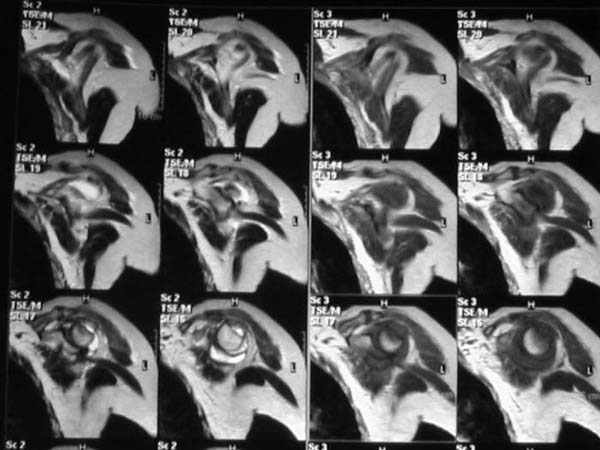

Активное отведение 80 гр., при пальпации - головка плечевой кости безболезненно вправляется и тут же самостоятельно вывихивается. Наложена косыночная иммобилизация, рентгенография (r3) и МРТ.В нашем диагностическом центре МРТ исследование плечевого сустава выполнено впервые, опыта у нас маловато :(.Вопросы: уточнение диагноза? какие исследования провести? тактика лечения?

МРТ1МРТ2МРТ3МРТ4

Из того, что видно на недостаточно качественно отсканированных МРТ - нижний подвывих плеча и синовиит. Непонятный очаг по заднему контуру головки плеча (то ли артефакт, то ли косой срез, проходящий между головкой и большим бугорком). Сухожилия вращательной манжетки выглядят целыми. Неправильная форма нижней части labrum glenoidale - разрыв ?

И еще одно пожелание - МРТ костно-суставной системы ОБЯЗАТЕЛЬНО нужно проводить с использованием сканов с подавлением сигнала от жировой ткани (SPIR - на Филипсах, у Вас, как я вижу - Филипс; FATSAT - на других томографах, либо STIR - есть на любых аппаратах). Только так можно увидеть отек мягких тканей и костного мозга на фоне жировой ткани.

Плоскости при сканировании плеча обязательно должно быть 3

1. Ортогональная поперечная (аксиальная)

2. Косая корональная (параллельно длинной оси диафиза)

2. Косая сагиттальная (так же параллельно диафизу плеча)

МРТ должен показать разрыв манжетки, но признаться я не большой эксперт по чтению МРТ сканов, хотя затемнение, отек мягких тканей по задней поверхности плеча видны Обычные рентгенограммы демонстрируют остеолизис в области большого бугорка.

Все-таки, должен признать, что такие снимки - суррогат. Информативность чуть-чуть лучше, за счет большего размера. С учетом сложных топографо-анатомических соотношений необходимо иметь картину всех срезов, и смотреть их поочередно, иначе не создается целостной картины, а также иметь возможность манипулировать контрастом. Вот если б снимки были в DICOME - тогда от интерпретации было бы не отвертеться -)

А так, могу только сказать следующее

1. На рентгене - нижний подвывих плеча и очаг остеолиза суставного бугорка с четкими контурами (вдавленный перелом на фоне остеопороза ? доброкачественная опухоль? аваскулярный некроз ? (хотя ни разу не слышал об аваскулярном некрозе плеча..)

2.выраженный выпот в полости сустава

3. Сказать о связках и сухожилиях что-то при снимках в таком режиме не берусь.